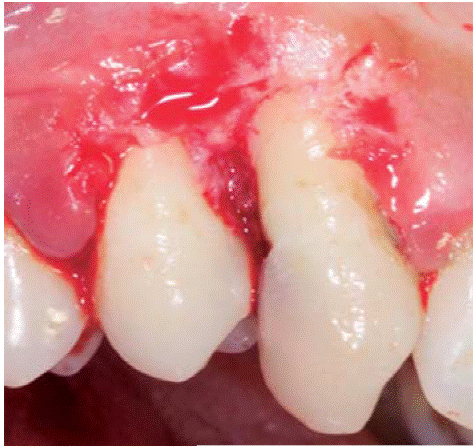

Al examen clínico se observa lesión gingival inflamatoria a nivel de piezas 3.4 y 3.5, de aproximadamente 15x9 mm, cubriendo la cara vestibular de la corona clínica, de consistencia firme, lobulada, textura rugosa y sangrante ante el estímulo (Figuras 1 y 2). A la evaluación periodontal no se detectaron bolsas periodontales, se observó presencia de placa, obteniéndose un índice de higiene oral (O'Leary) de 18.75%.

Al examen radiográfico se observo ausencia de contacto interproximal entre las piezas 3.4 y 3.5 y material restaurador en zona interproximal (Figura 3).